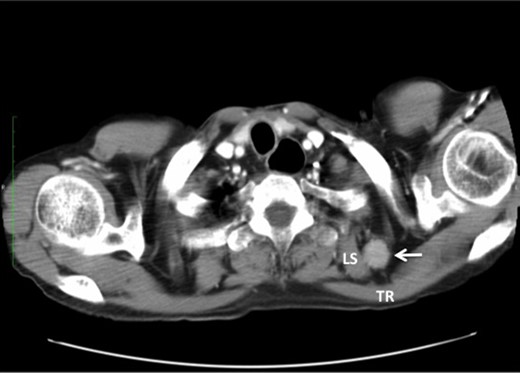

A 76-year-old male underwent screening endoscopy because of a history of gastrectomy for cancer, which showed a superficial and protruding tumor in the mid-thoracic esophagus. Histological examination of the biopsy specimen confirmed well-differentiated squamous cell carcinoma. A computed tomography (CT) scan of the neck, chest and abdomen showed no evidence of metastatic disease. The tumor was clinically staged as T1bN0M0 according to the American Joint Committee on Cancer [1]. He received concurrent chemoradiotherapy at a dose of 60 Gy with low-dose 5-fluorouracil. Four months after completion of chemoradiotherapy, however, the primary tumor relapsed with mediastinal LNM and right SCNM. Right transthoracic esophagectomy with mediastinal and right cervical lymphadenectomy was performed as a salvage treatment. Two months after esophagectomy, a right neck tumor developed that was palpable at the posterior triangle, close to the anterior border of the trapezius muscle. A CT scan of the neck showed a heterogeneously enhanced tumor 25 mm in diameter located between the trapezius muscle and the levator scapulae muscle (Fig. 1). En bloc dissection of the adipose tissue including the tumor and the transverse cervical artery was performed. Histological examination revealed that 5 of the 22 retrieved lymph nodes had metastatic squamous cell carcinoma. The patient received adjuvant radiotherapy of 50.4 Gy to the area of dissection; however, died of pneumonia 11 months after metastasectomy, with locally recurrent disease that invaded right brachial plexus.

Note that the transverse cervical vessels (*) were involved in the tumor (arrow). TR, trapezius muscle; LS, levator scapulae muscle.